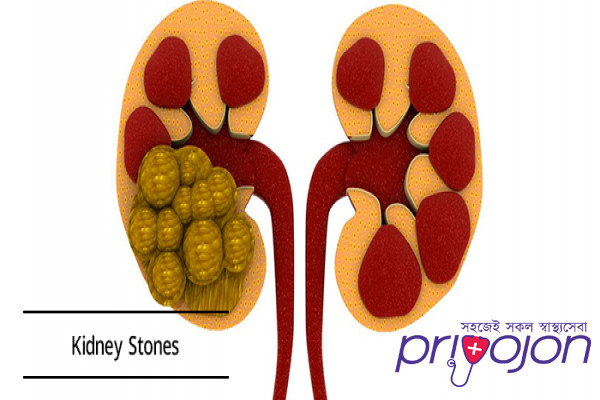

Kidney stone disease, also known as urolithiasis, is when a solid piece of material (kidney stone) develops in the urinary tract.[2] Kidney stones typically form in the kidney and leave the body in the urine stream.[2] A small stone may pass without causing symptoms.[2] If a stone grows to more than 5 millimeters (0.2 in), it can cause blockage of the ureter, resulting in severe pain in the lower back or abdomen.[2][7] A stone may also result in

A urinary calculus may be a crystalline and hard mineral material that gets formed within the kidney or in our tract . Kidney stones are a standard explanation for hematuria (blood in urine) and sometimes cause severe pain within the abdomen, groin or within the flank. Kidney stones also are called renal calculi. Urinary stones, mostly develop in patients who are betw